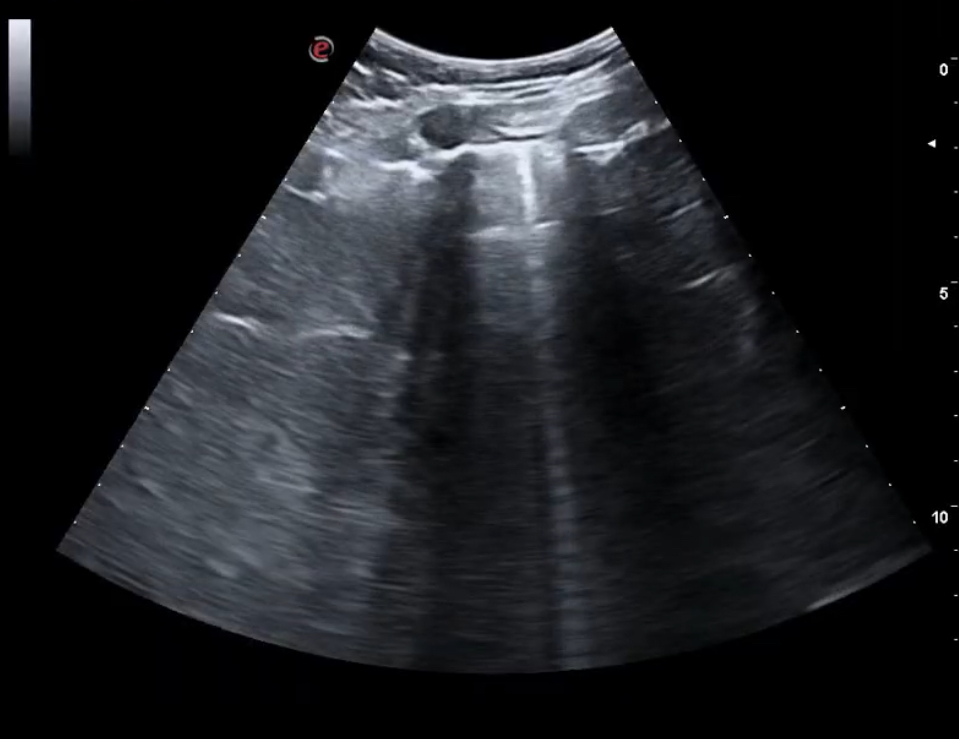

Se decidió realizar ecografía clínica pulmonar apreciándose líneas B en campos 2-4-6 de ambos pulmones con derrame en ambos senos costofrénicos visualizándose la cola de sirena y vena cava congestiva. La ecocardiografía realizada por los cardiólogos no mostró defectos en la contractilidad.